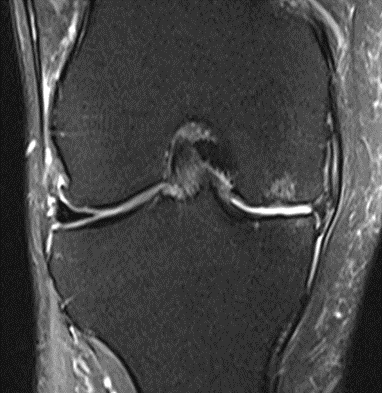

MRI scans illustrating the improvements regarding Group 2 are presented below, showing pre-treatment images with evident cartilage defects, pronounced bone marrow edema, and synovial inflammation, followed by post-treatment scans demonstrating improved joint structure, reduced edema, and decreased inflammation (Figures 12-29).

MRIs of Group 2

Figure 12: Female, 59 years, pre-intervention MRI.

Figure 13: Female of figure 12, 59 years, two-month follow-up MRI: MSC plus ChondroFiller® liquid.